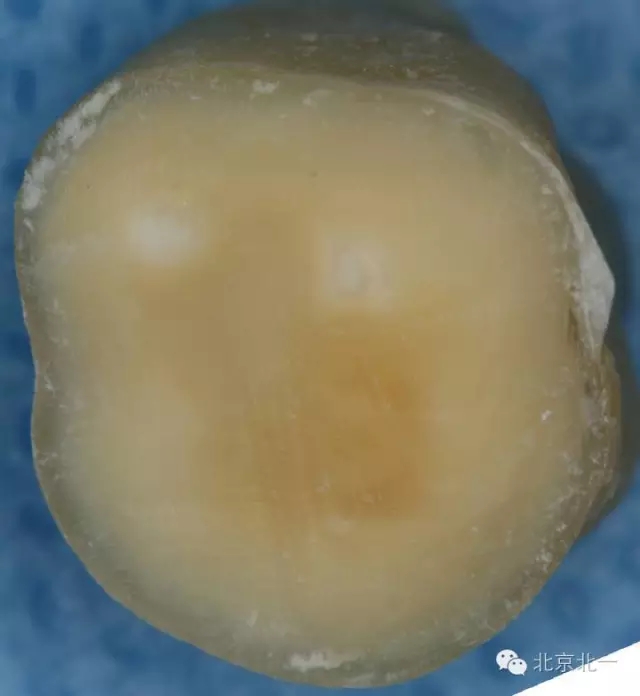

這只是因?yàn)閷W(xué)生們對(duì)于牙體組織的顏色沒有很好的理解,髓頂?shù)纳珴膳c其下方髓底的顏色有著顯著的不同(下圖為同一顆牙不同層面的片切圖 A為髓頂與穿髓孔B為下方的髓底與根管口)。